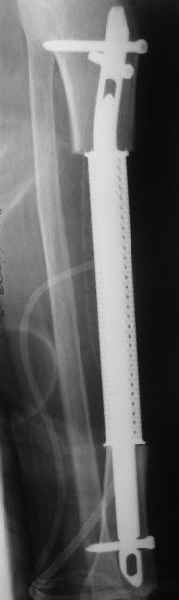

Больную положили к нам в отделение. Заказали кейдж в МАТИ (посодействовал

Анатолий Федорович Лазарев, ему огромное спасибо), его быстро

сделали. На этой неделе состоялась операция - сделали сегментарную

резекцию единым блоком. Кортикальная пластинка вроде не не была нигде

прорвана, хотя местами сильно истончена.

Пока делали остеосинтез, препарат успели отправить в лабораторию, так

что распилить получилось только на следующий день.

При его рассмотрении с рентгенологом и морфологом сошлись, что это не

фиброзная дисплазия, что было первым предположением по рентгенограммам. В

полости было и мягкотканое образование. Окончательно заключение дадут

через несколько дней. Будем признательны за комментарии и критику.